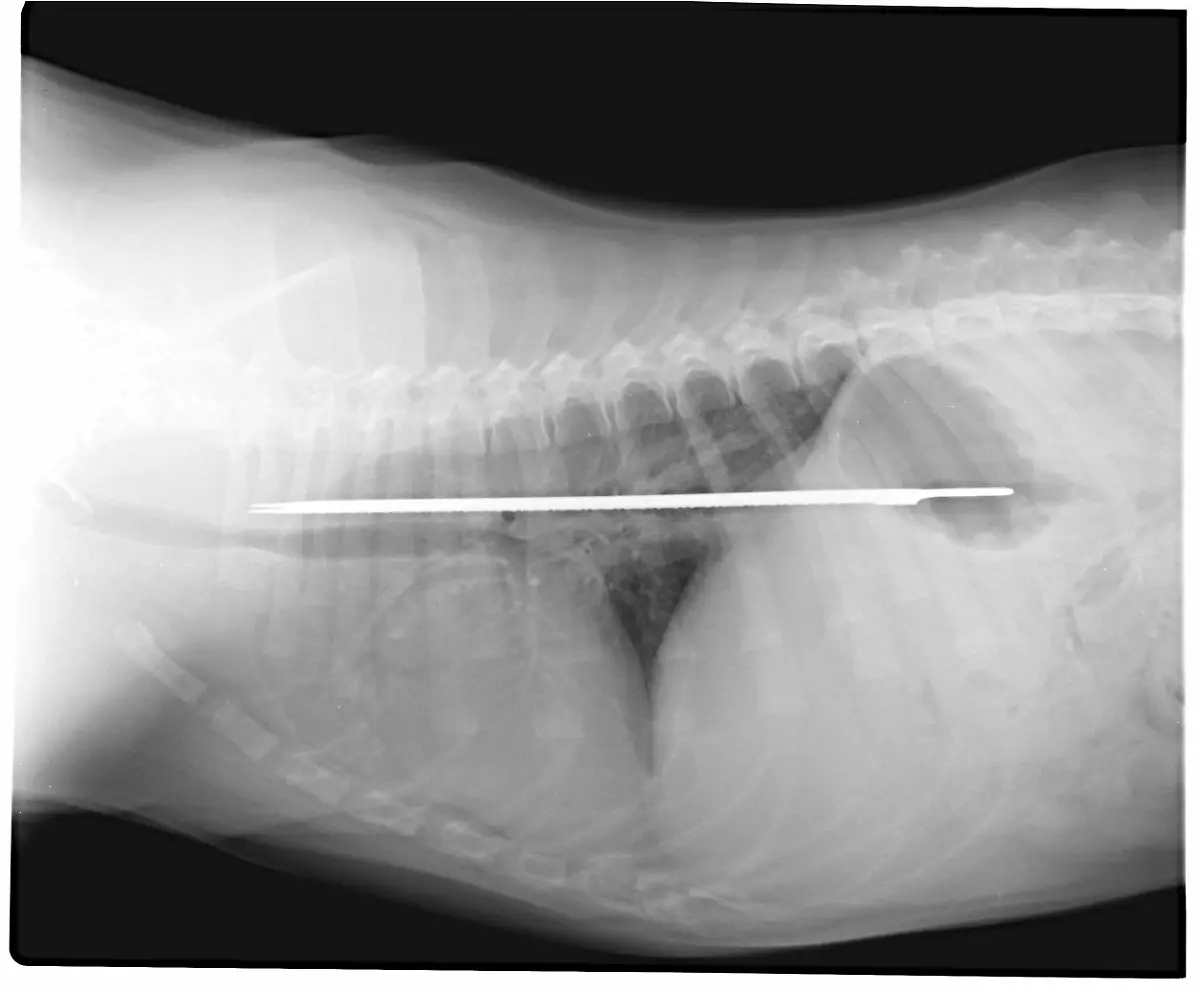

Socken, Kieselsteine, Außerirdische - Röntgenbilder von Mägen US-amerikanischer Haustiere zeigen die skurrilsten Gegenstände. Eine Zeitschrift zeichnet jedes Jahr die außergewöhnlichsten Aufnahmen aus.